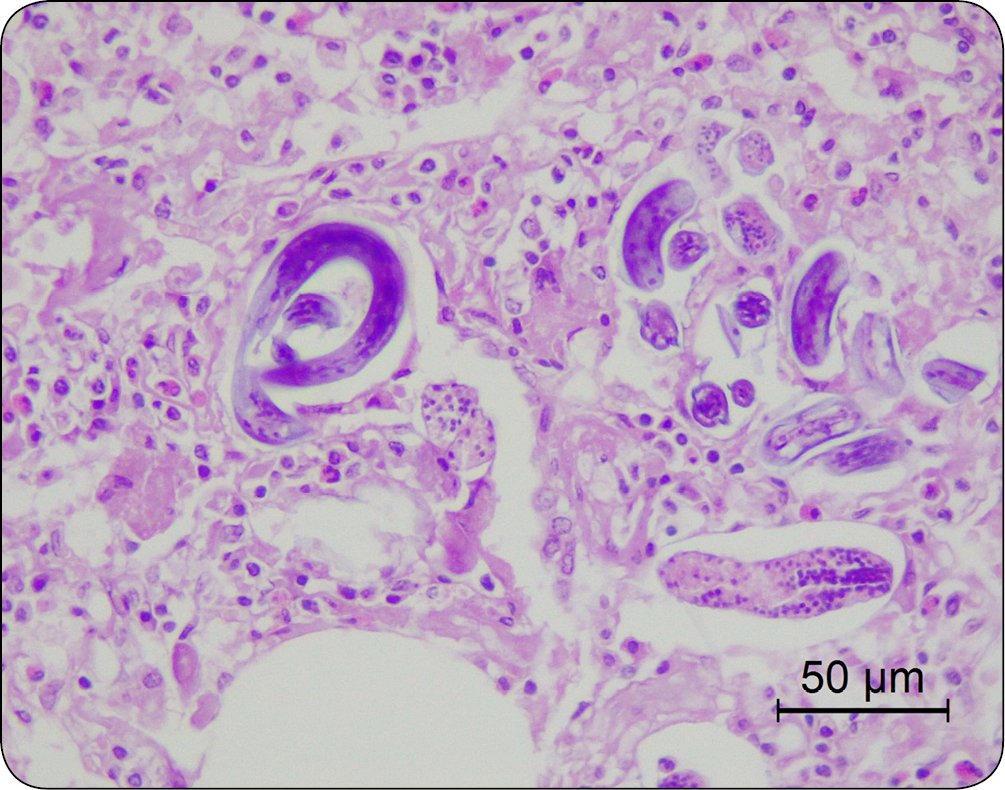

Nadciśnienie płucne może być wywołane zarówno obecnością pasożytów w prawej komorze serca i tętnicy płucnej (Dirofilaria immitis; ryc. 5), jak i w tkance płuc (nicienie płucne; ryc. 6). Ze względu na złożony mechanizm wywoływanych zmian infestacje pasożytnicze nie są zaliczane do typowo zapalnych przyczyn nadciśnienia płucnego (typ 3) (2). Obecność pasożytów może skutkować zapaleniem drobnych tętniczek płucnych, epizodami zatorowo-zakrzepowymi, a także cechami zapalenia płuc (2). Ten typ nadciśnienia płucnego jest wyjątkowy w medycynie weterynaryjnej, jako że ludzie nie są narażeni na rozwój PH w efekcie obecności Dirofilaria immitis czy Angiostrongylus sp. (2).